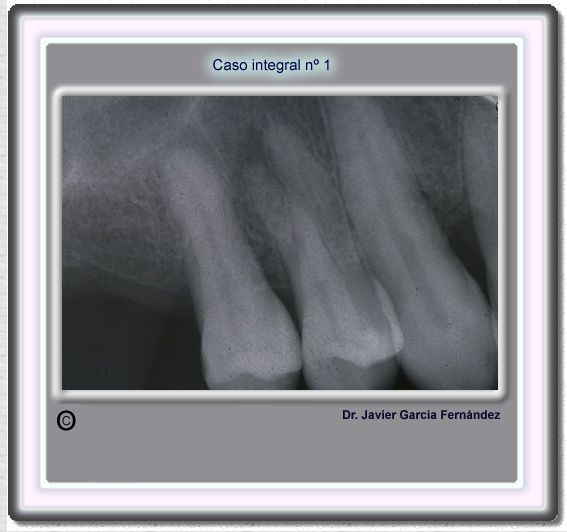

image 15